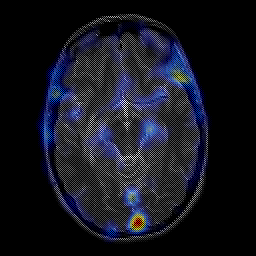

overlay -- Slice #11

[Home][Help][Clinical] Slice 11